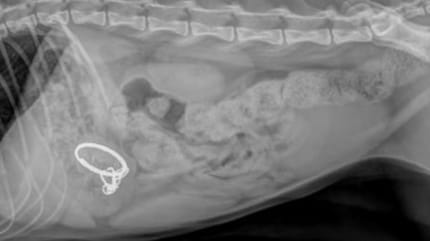

Radiographie du chat Haru

Haru est immédiatement transporté à la clinique vétérinaire. Lorsque les médecins examinent la radiographie, ils deviennent blêmes. L'estomac du chat contient d'autres morceaux tranchants de l'appareil détruit. Il risque une occlusion intestinale, et donc une mort atroce.

Plus choquant encore, la découverte des vétérinaires : Haru a dû avaler le pointeur laser avant même son arrivée au refuge, soit il y a au moins dix jours. Pendant dix jours, il a gardé ces débris dangereux dans son ventre sans jamais se plaindre.